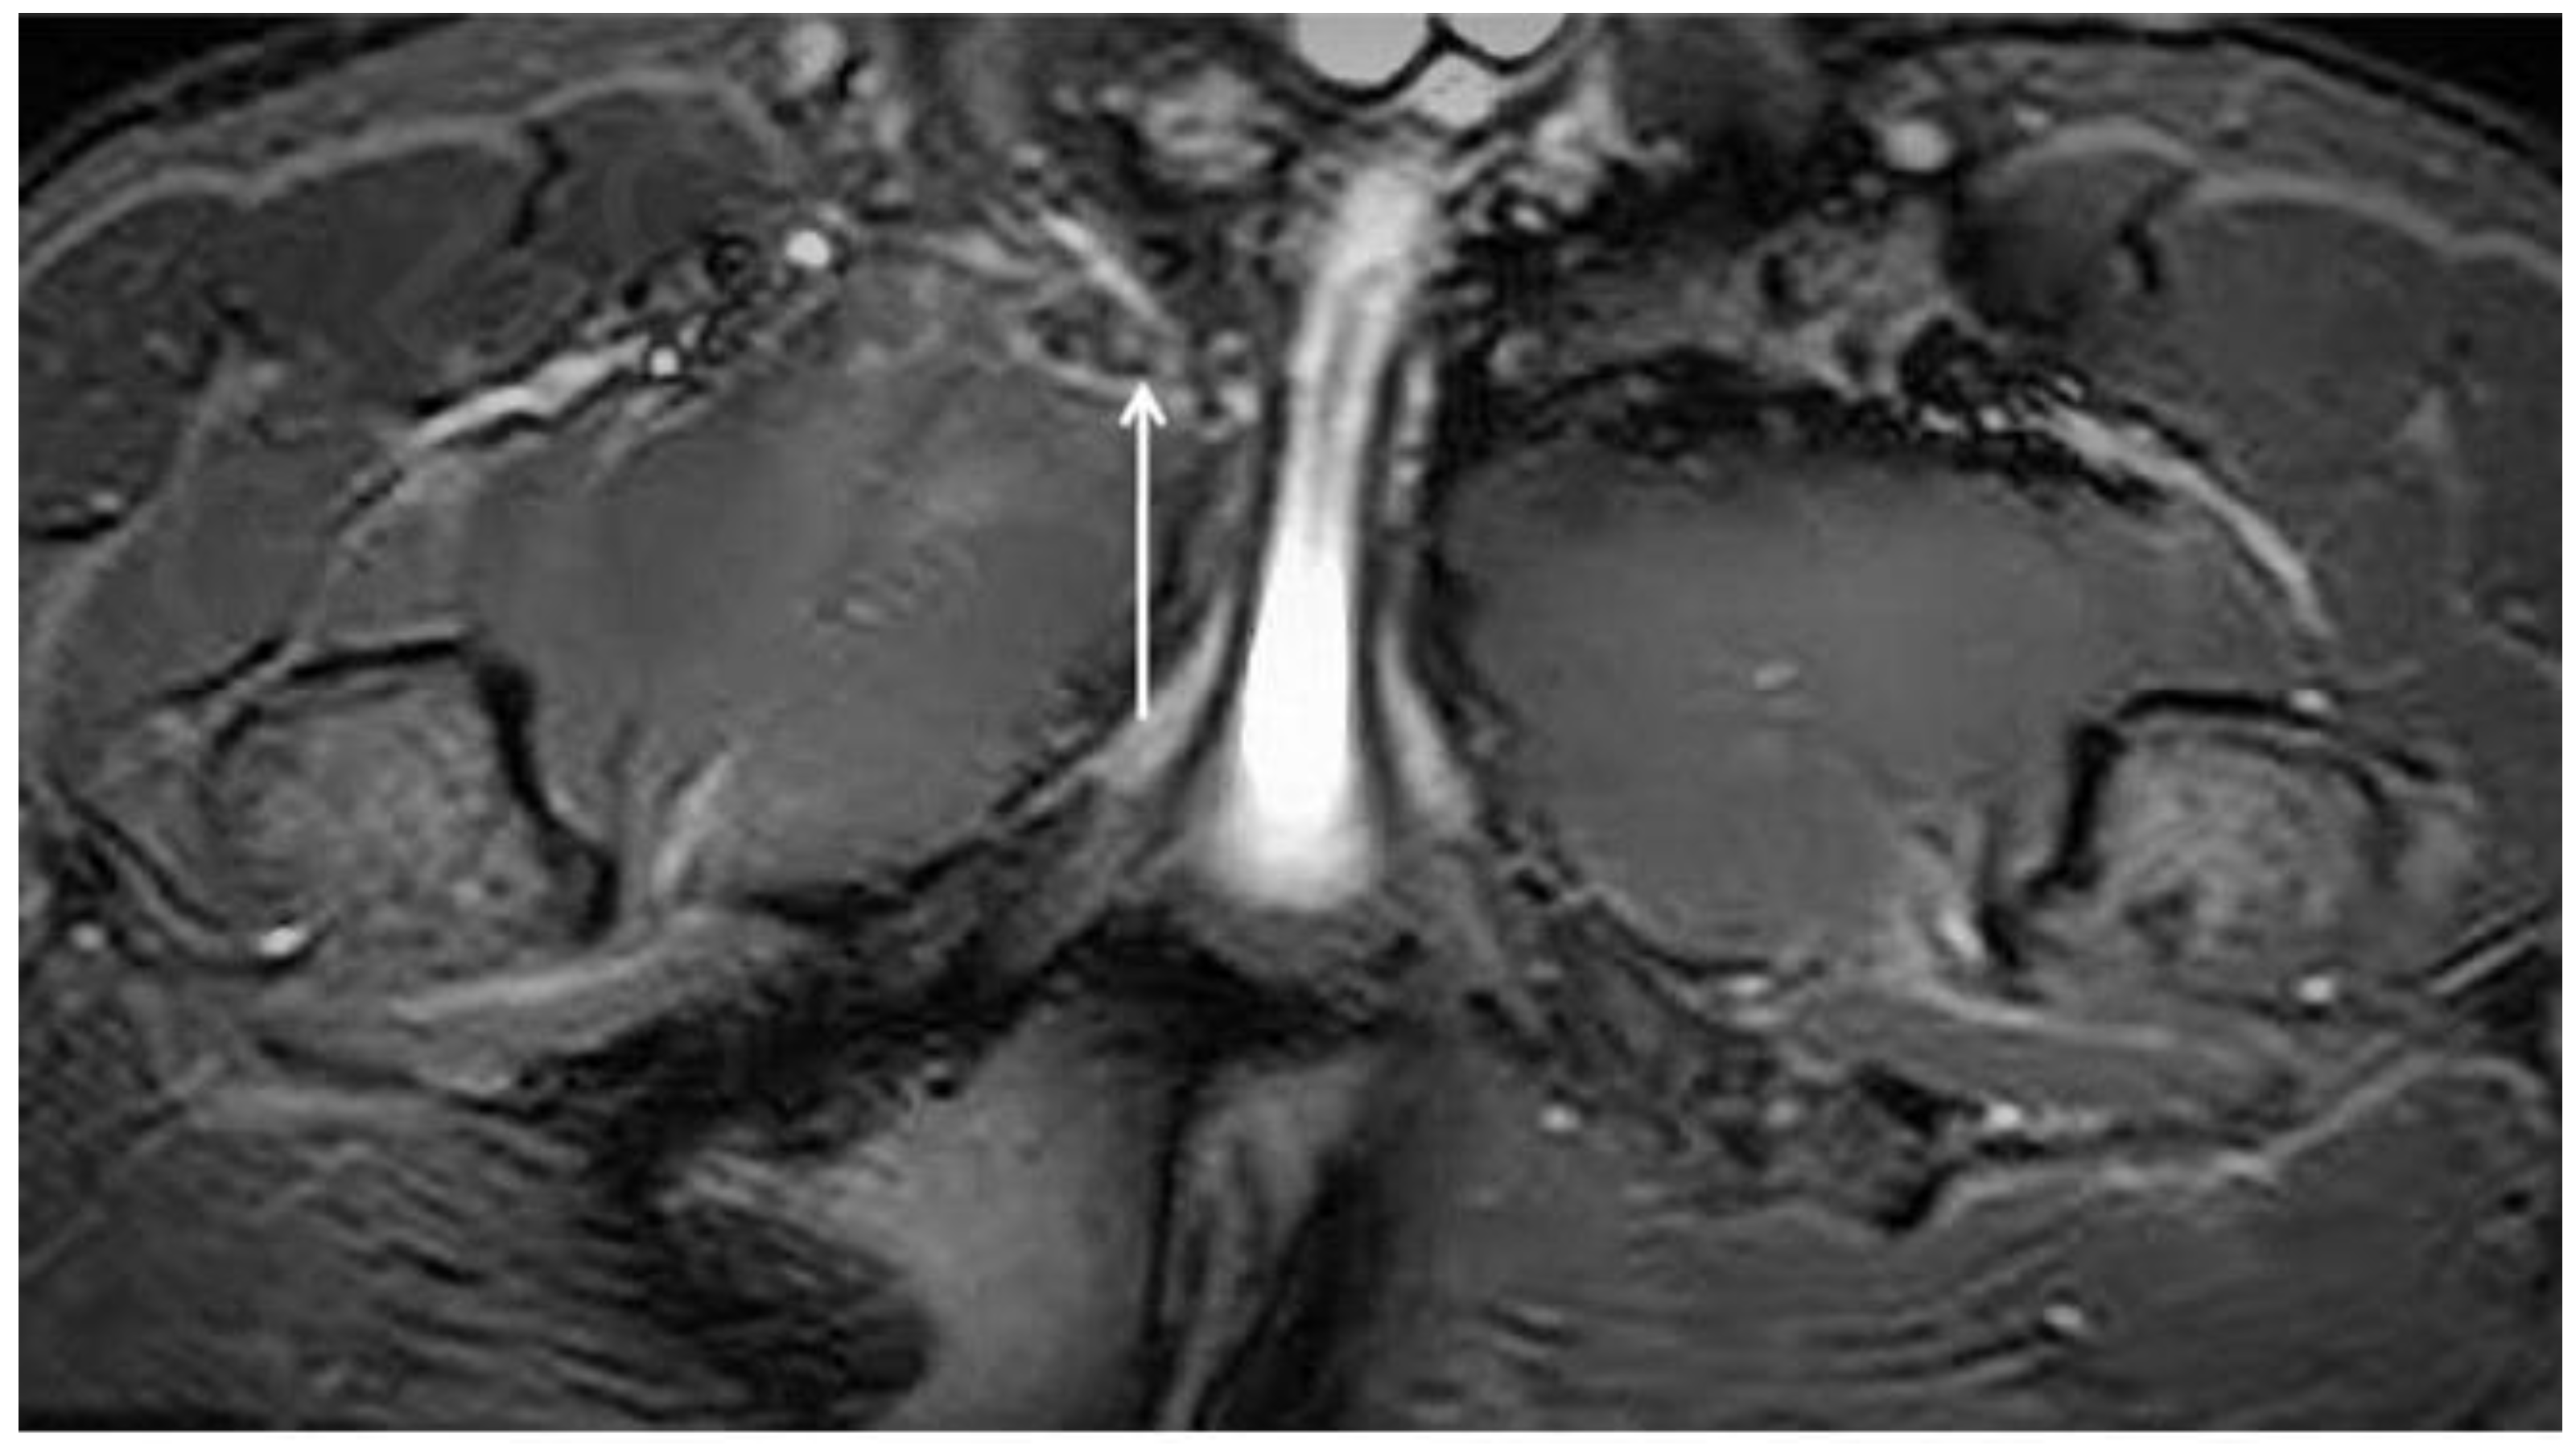

| Bone marrow oedema | Coronal T1; coronal T2 FS; axial oblique T2 FS; axial oblique PD FS | Signal hyperintensity in the fluid-sensitive sequences. Signal hypointensity in T1 sequences. Grade 1: BMO ≤ 1 cm; Grade 2: BMO ≥ 1 cm and ≤2 cm; Grade 3: BMO ≥ 2 cm. |